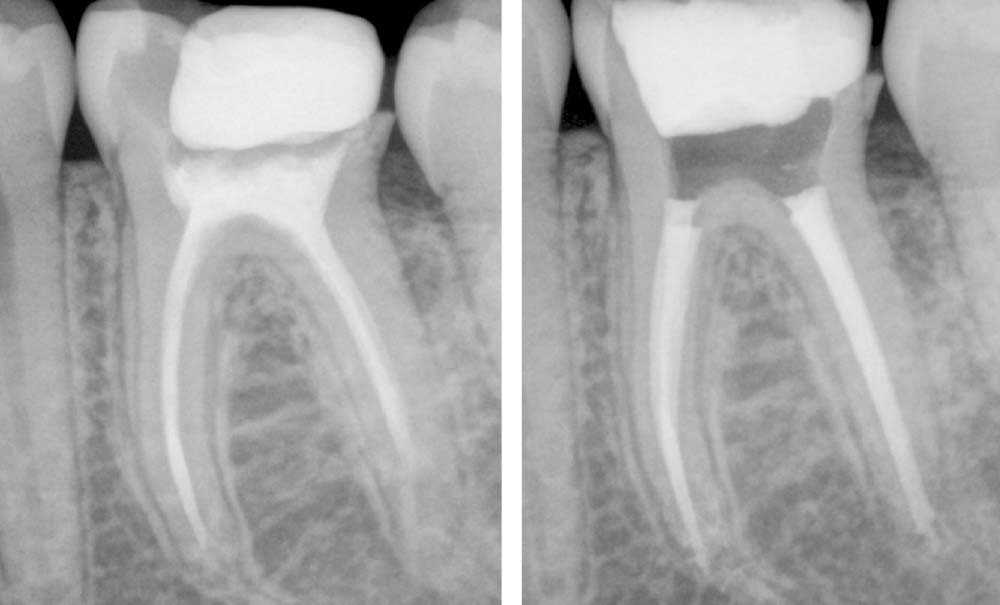

La désobturation. Comment réaliser une désobturation efficiente ? Qui enlève un maximum de gutta sans compromettre l’intégrité dentinaire (butée, fausse route…) ? Désobturation mécanisée ? Manuelle ? Avec ou sans solvant ?

La perméabilité. Si elle a longtemps fait débat dans la littérature [4], elle permet aujourd’hui de sécuriser la trajectoire canalaire, de s’assurer de la vacuité du canal, et d’obtenir la longueur de travail. Comment s’assurer de la bonne reproductibilité de sa longueur de travail ? Vérification avec le localisateur d’apex ? Vérification radiographique ? Les deux ?

L’instrumentation (fig. 4). À l’instar de la cavité d’accès, le travail instrumental se doit d’être aussi petit que possible, aussi large que nécessaire, même dans un contexte de réintervention. Les canaux ayant déjà été préparés, il faudra s’adapter à la situation clinique : si les canaux étaient sous-préparés, un élargissement canalaire sera indispensable afin d’obtenir un volume suffisant pour désinfecter correctement. Si les canaux étaient surpréparés, un élargissement canalaire ne sera peut-être pas nécessaire. La réintervention nécessite-t-elle une certaine conicité instrumentale ? Une certaine largeur de travail (diamètre apical) ? Ai-je bien éliminé les anciens biomatériaux d’obturation ?

La désinfection (fig. 5). L’anatomie canalaire est bien plus complexe qu’il nous est permis de la visualiser cliniquement ou radiographiquement. D’un tronc principal (le canal) peuvent partir de nombreuses arborescences : canaux latéraux, canaux secondaires, canaux accessoires, delta apicaux, isthmes, sillons, etc. [5]. L’anatomie des canaux principaux n’est elle-même pas simple, avec une forme ovale dans la plupart des cas, mais qui peut également être conique, pyramidale, en ruban (ou aplati), en huit, en C, trapézoïdal, en goutte d’eau, etc. [6]. Nos instruments de préparation imprimant une forme ronde, cela ne concorde pas avec l’anatomie canalaire, dont 55 % des surfaces peuvent ne pas être touchées. Cela engendre des débris non nettoyés (smear layer, tissu pulpaire inflammatoire ou nécrosé, biofilm bactérien, toxines, etc.) [7] pouvant être responsables d’infection secondaire [3]. L’instrumentation canalaire n’est donc pas suffisante pour la désinfection canalaire ; elle a pour rôle de créer un volume canalaire pour les irrigants. Quels irrigants utiliser ? Avec quel matériel apporter les irrigants au sein des canaux ? Faut-il activer la solution d’irrigation ? Jusqu’où amener l’irrigant par rapport à la longueur de travail ?

L’obturation canalaire (fig. 6). Il est impossible de rendre un canal stérile, malgré le travail d’instrumentation et de désinfection. L’obturation canalaire aura donc pour rôle de combler un maximum de volume endodontique afin d’empêcher la percolation bactérienne coronaire, afin d’entomber les bactéries restantes intracanalaires, de sceller la porte de sortie apicale (dont les fluides, par exemple en cas de lésion apicale, peuvent remonter au niveau canalaire et constituer un apport nutritif pour les bactéries).